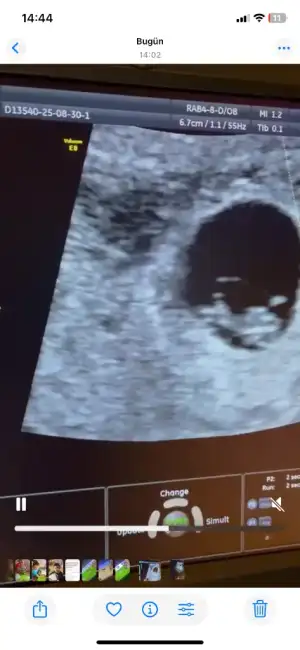

6 haftalik karından ultrasyon tahminde bulunabilir misiniz

• IMG_20250312_094215.webp

IMG_20250312_094215.webp

21,9 KB · Görüntüleme: 58